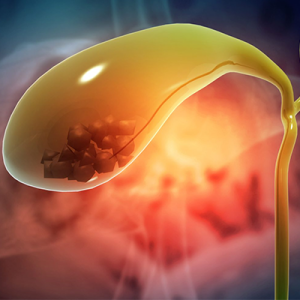

Read MoreHPB – Gall bladder

Minimally invasive surgery for gallstones, infections, and other gallbladder issues.